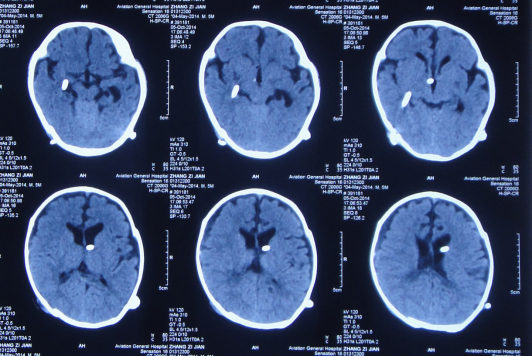

患儿3月龄时入我院,神智清楚,精神可,体温不高,双眼下视(落日征)明显,囟门彭隆,头围增大至41cm,CT:脑积水。

脑室外引流术前头颅核磁共振检查,脑室系统全增大。